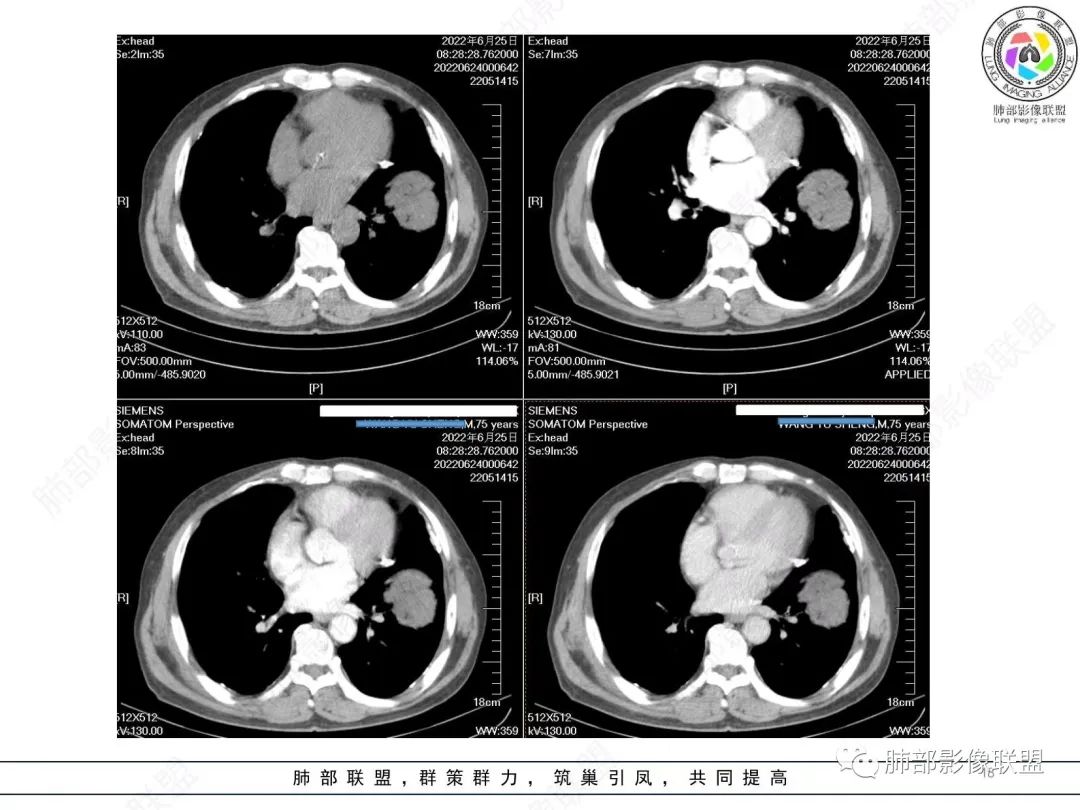

左肺上叶大肿块,膨胀性生长,边界清,密度较低,见部分坏死区,强化弱,肿块见支气管充气V扩张征,分布僵直,枯树枝特点,另一个重要特点血管造影征,淋巴瘤,肿块长轴与胸膜平行,与隐球菌鉴别,隐球荚膜抗原检查,明确诊断经皮肺穿刺。另胸膜钙化(问诊既往有无患胸膜炎病史)。

如果粘液腺Ca,周边太干净了,不支持。

老年男性,糖尿病病史,消瘦、乏力三个月,影像表现左肺上叶胸膜下团块,有一定张力,内部疏松,可见支气管影及坏死区,增强病灶边缘环形强化,内部未见强化,考虑炎性肉芽肿病变,隐球?奴卡?放线菌?鉴别淋巴瘤。

左肺上叶胸膜下肿块,宽基底与胸膜相连,跨叶裂,边缘清晰膨隆,其内支气管充气,部分扩张、僵直,无明显强化,血管造影征,考虑淋巴瘤,鉴别腺癌

左肺胸膜下巨大占位,跨叶裂,宽基底与胸膜相连,胸膜钙化,平扫密度较低,强化不明显,可见内部血管显影,支气管充气征和扩张,考虑为恶性,倾向于淋巴瘤

增强没有强化,血管束正常,气管束有正常有扩张,内有空洞,考虑炎性病变,隐球?

左侧胸腔巨大肿块,跨叶生长,临近胸膜钙化,边缘模糊,可见支气管影,定位肺内,增强后轻度强化,边缘见血管影,考虑淋巴瘤,鉴别肉瘤

老年,明显消瘦,左侧胸廓轻度缩小?胸膜增厚,见钙化,以前结核?接触其他?整个肿块膨隆,坏死不明显,支气管通畅,轻度扩张轻度强化,考虑恶性,淋巴瘤可能

左肺上叶胸膜下肿块,膨胀性生长,边界清晰,密度不均部分坏死,未见强化,病灶内支气管迂曲扩张,病灶长轴与胸膜平行,胸膜下脂肪间隙存在,胸膜钙化,考虑放线菌?毛霉?鉴别淋巴瘤

支持淋巴瘤,左上肺大肿块,有分叶,边缘光整,病灶内密度不均,可见支气管扩张征,增强后可见血管影征。周围肺野清晰。

左肺上叶肿块,宽基底与胸膜相连,跨叶裂,边缘清晰膨隆,可见小分叶,其内支气管充气,部分扩张、僵直,呈枯枝征,支气管达边征,增强无明显强化,可见血管造影征,考虑恶性病变,淋巴瘤,鉴别粘液腺癌。

左肺团块样病灶,分叶,膨隆,不规则空洞,支气管枯枝样,血管造影征,考虑恶性,腺癌(肺肠型)。